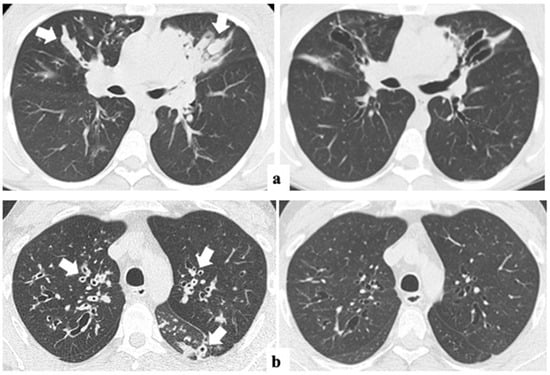

The median time interval between CT0 and CT1 was 2.5 ± 1.5 years (range from 12 to 54 months). The changes in the global Bhalla score and each specific structural subscore before and after ETI are summarized in Table 2. The global Bhalla score improved significantly (p < 0.001), from 12.2 (±2.8) to 14.0 (±2.8). Additionally, other radiological items, such as peribronchial thickening (1.4 ±0.6 vs. 1.0 ±0.4) and the extent of mucus plugs (1.6 ±0.7 vs. 0.8 ±0.6), also showed significant changes (p < 0.001) (Figure 2). None of the other parameters assessed worsened after one-year ETI.

Figure 2.

Axial lung CT images before (left) and after one-year ETI therapy (right) in two adults with CF. Dramatic improvements in mucus plugs in (a) (arrows) and peribronchial thickening in (b) (arrows) are shown. ETI: elexacaftor–tezacaftor–ivacaftor.

Similarly, BMI (22.4 ± 2.6 vs. 23.6 ± 2.6 kg/m2) and spirometry (ppFEV1 66.5 ± 19.8 vs. 77.0 ± 20.4, and ppFVC 80.6 ± 16.4 vs. 91.6 ± 14.1) showed significant improvements (p < 0.05).